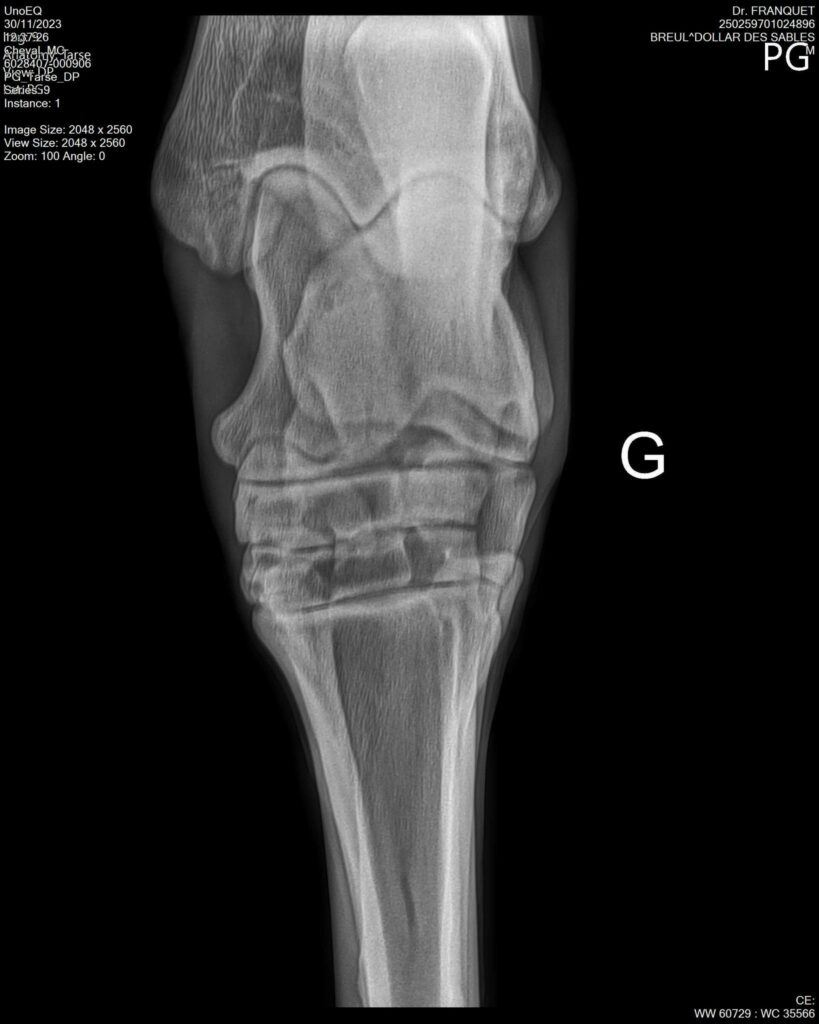

DOLLAR DES SABLES, Selle Français, hongre, 12 ans par DOLLAR DE MURIER x ABKE (ACORADO). Classé 135 avec professionnel à fait 125 avec amateur, récemment classé sur amateur 1GP 120. Très beau modèle ! Gentil cheval, respectueux avec des moyens et du sang. Transport OK, maréchalerie OK, santé RAS, Bilan clichés radios OK.

RADIOS